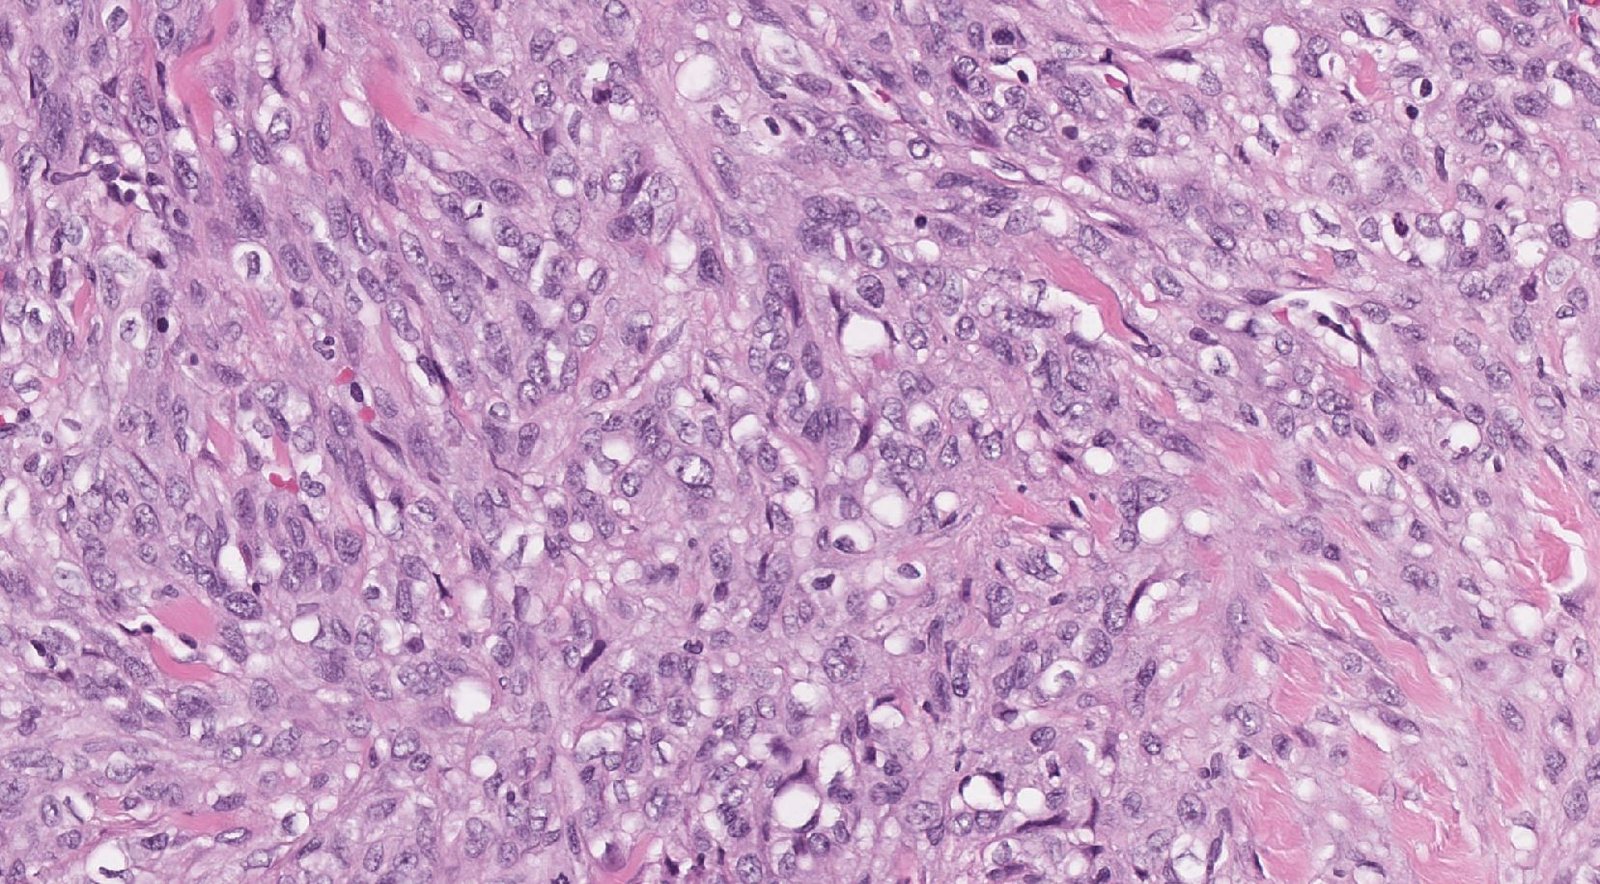

Case: ArmLesion

Final Diagnosis: